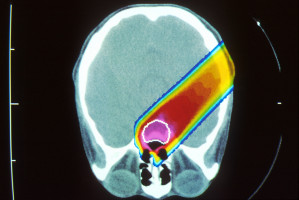

Proton therapy is an advanced type of radiation treatment that uses a beam of protons to deliver radiation directly to the tumour, destroying cancer cells while sparing healthy tissues.

Protons enter the body with a low radiation dose and stop at the tumour, matching its shape and volume or depth.

They deposit the bulk of their cancer-fighting energy right at the tumour, thereby reducing the dose to cardiopulmonary structures, which impacts the toxicity, functional status, quality of life and even survival for patients, explained Chang.